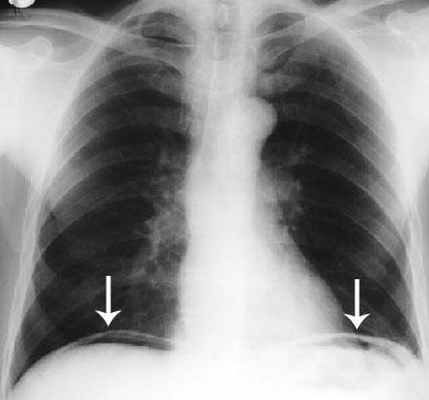

Рентгенография пассажа бария позволяет выявить препятствия на пути продвижения контрастного препарата, участки сужений и супрастенотического расширения кишки. Во время эндоскопического исследования врач производит биопсию для последующей морфологической верификации диагноза. В сложных для диагностики случаях проводят селективную ангиографию брюшной полости.

- Рентгенографию грудной клетки;

При подозрении на перфорацию тонкой кишки обзорная рентгенография органов брюшной полости обнаруживает свободный газ в подциафрагмальном пространстве, во время пункции брюшной полости или лапароскопического исследования обнаруживают кишечное содержимое в брюшной полости. Однако отсутствие названных патологических явлений не свидетельствует об отсутствии перфорации. Поэтому при наличии соответствующей клиники больному показана срочная лапаротомия, во время которой устанавливается окончательный диагноз.

Главным рентгенологическим симптомом острой кишечной непроходимости является появление чаш Клойберга — горизонтальных уровней и куполообразных участков просветления (газов) над ними. Окончательный диагноз устанавливают во время лапаротомии.